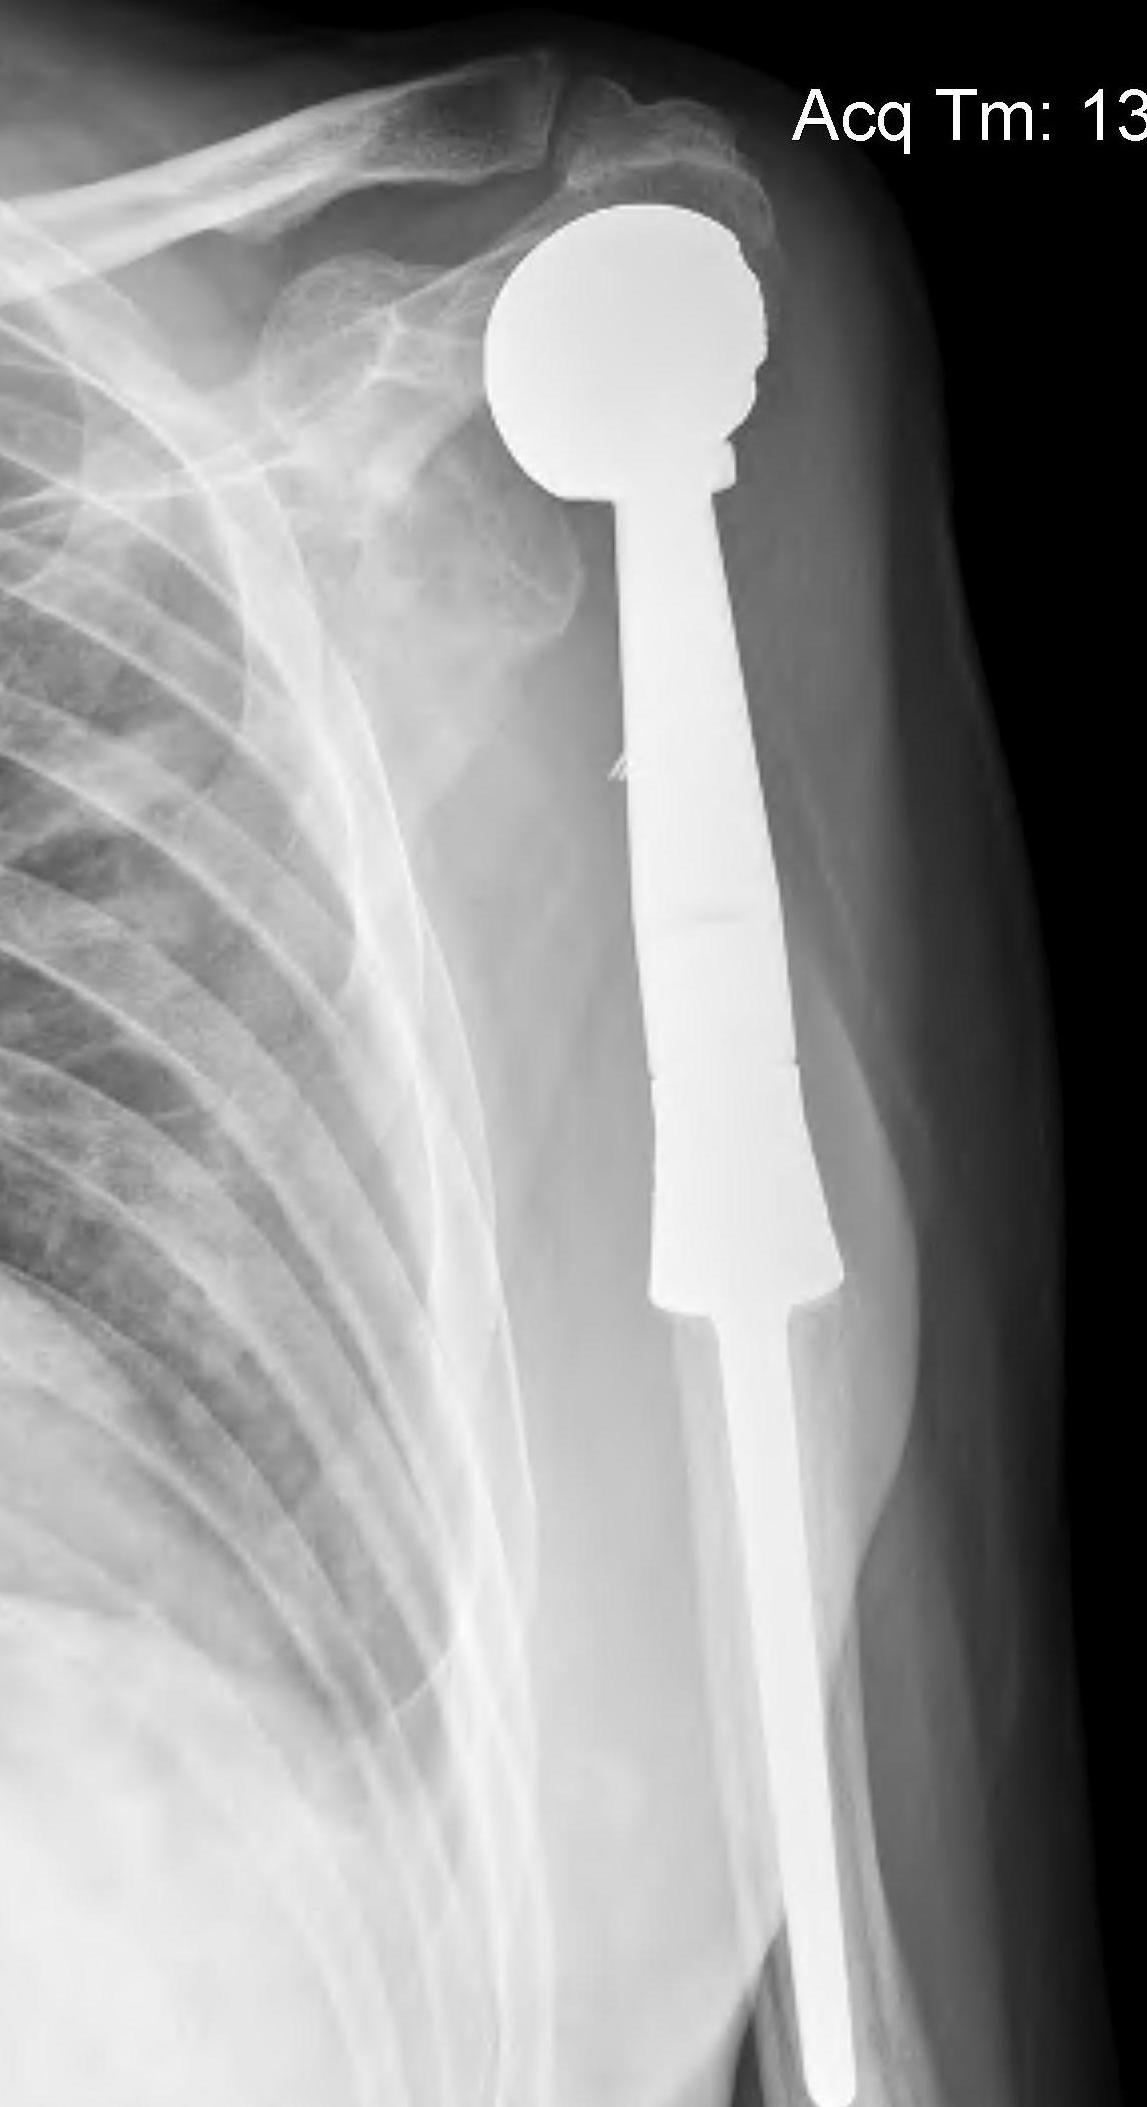

Proximal Humerus

Options

ORIF with plate +/- cement

IMN +/- cement

Tumour prosthesis

Results

Wu et al J Orthop Traumatol 2023

- 45 patients with proximal humerus metastasis

- IM nailing + cement versus plate

- lower blood loss and shorted hospital stay with IMN

- better pain relief with IMN